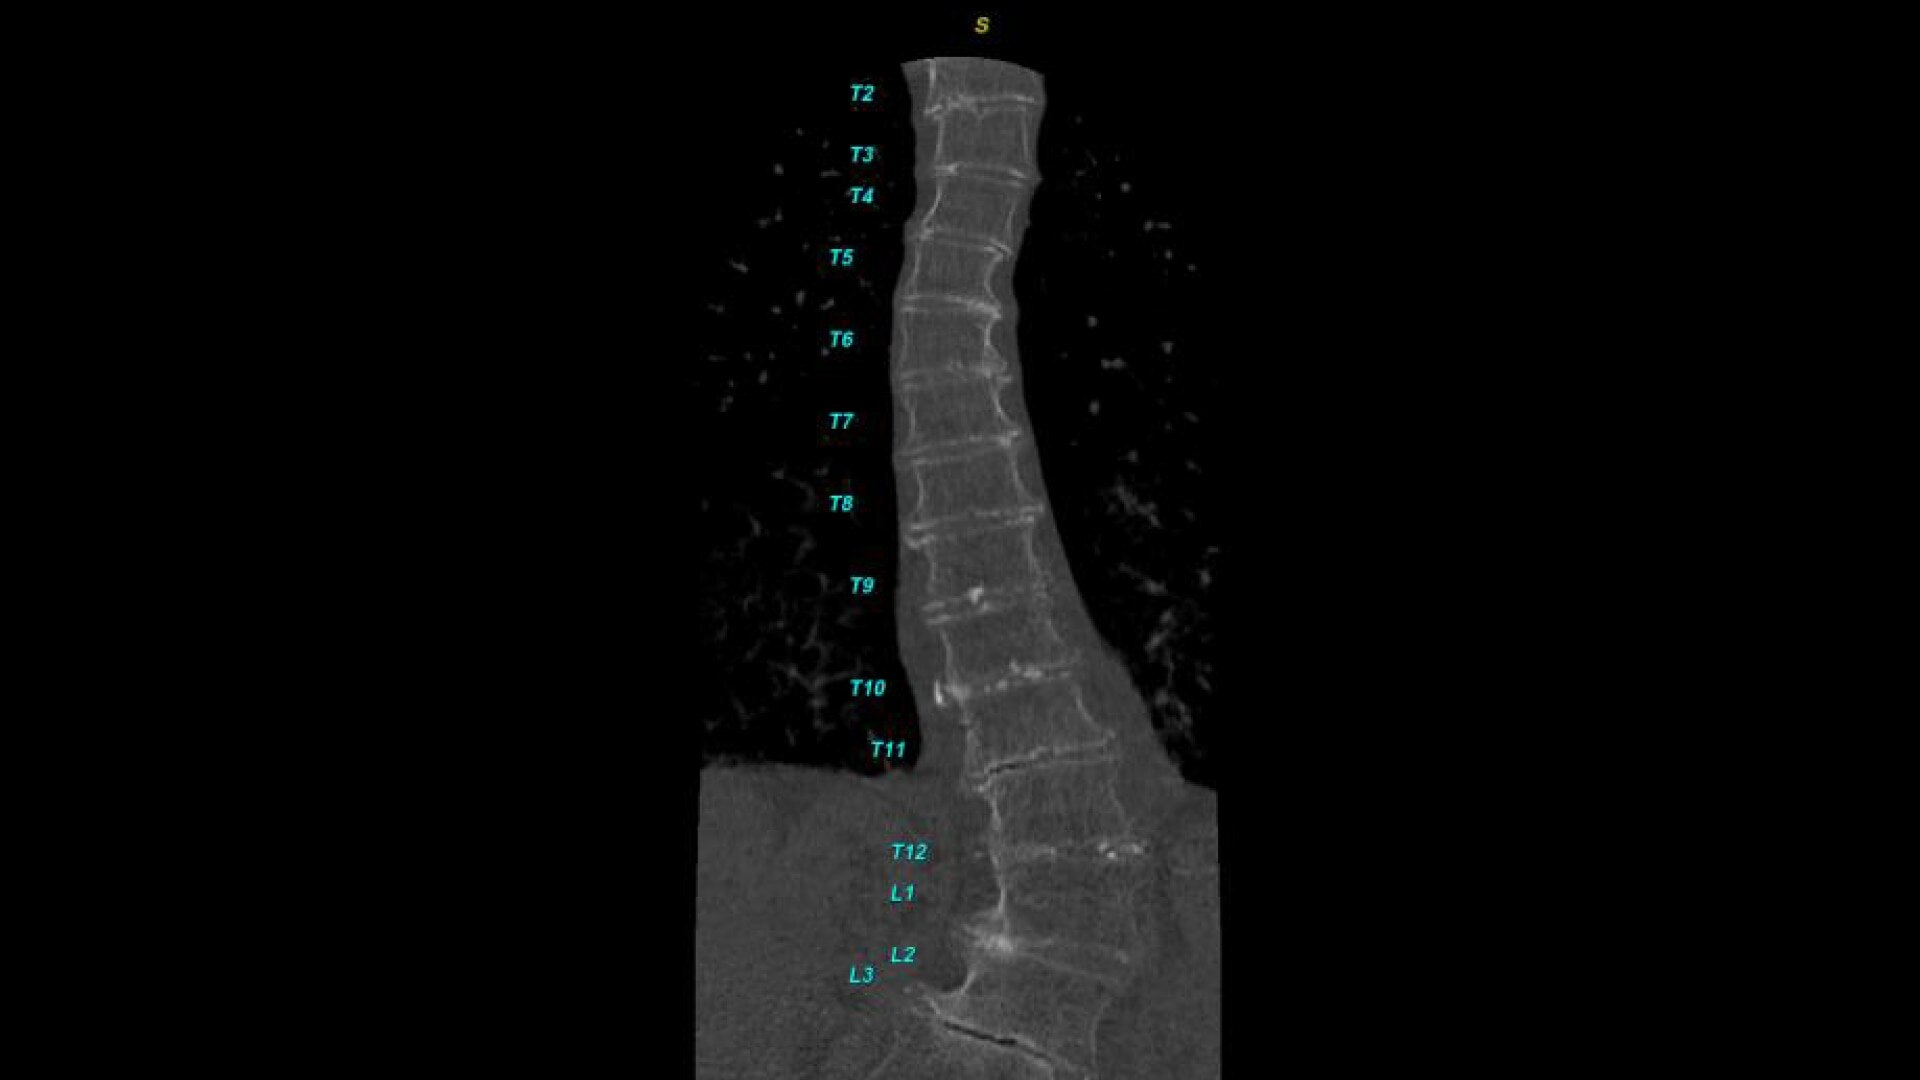

Automated curved reformats to aid in rapid reading and reporting.

• Automated generation of a 3D trace to generate oblique and straightened reformat views

• Automated generation of oblique views perpendicular to vertebral bodies and disc spaces